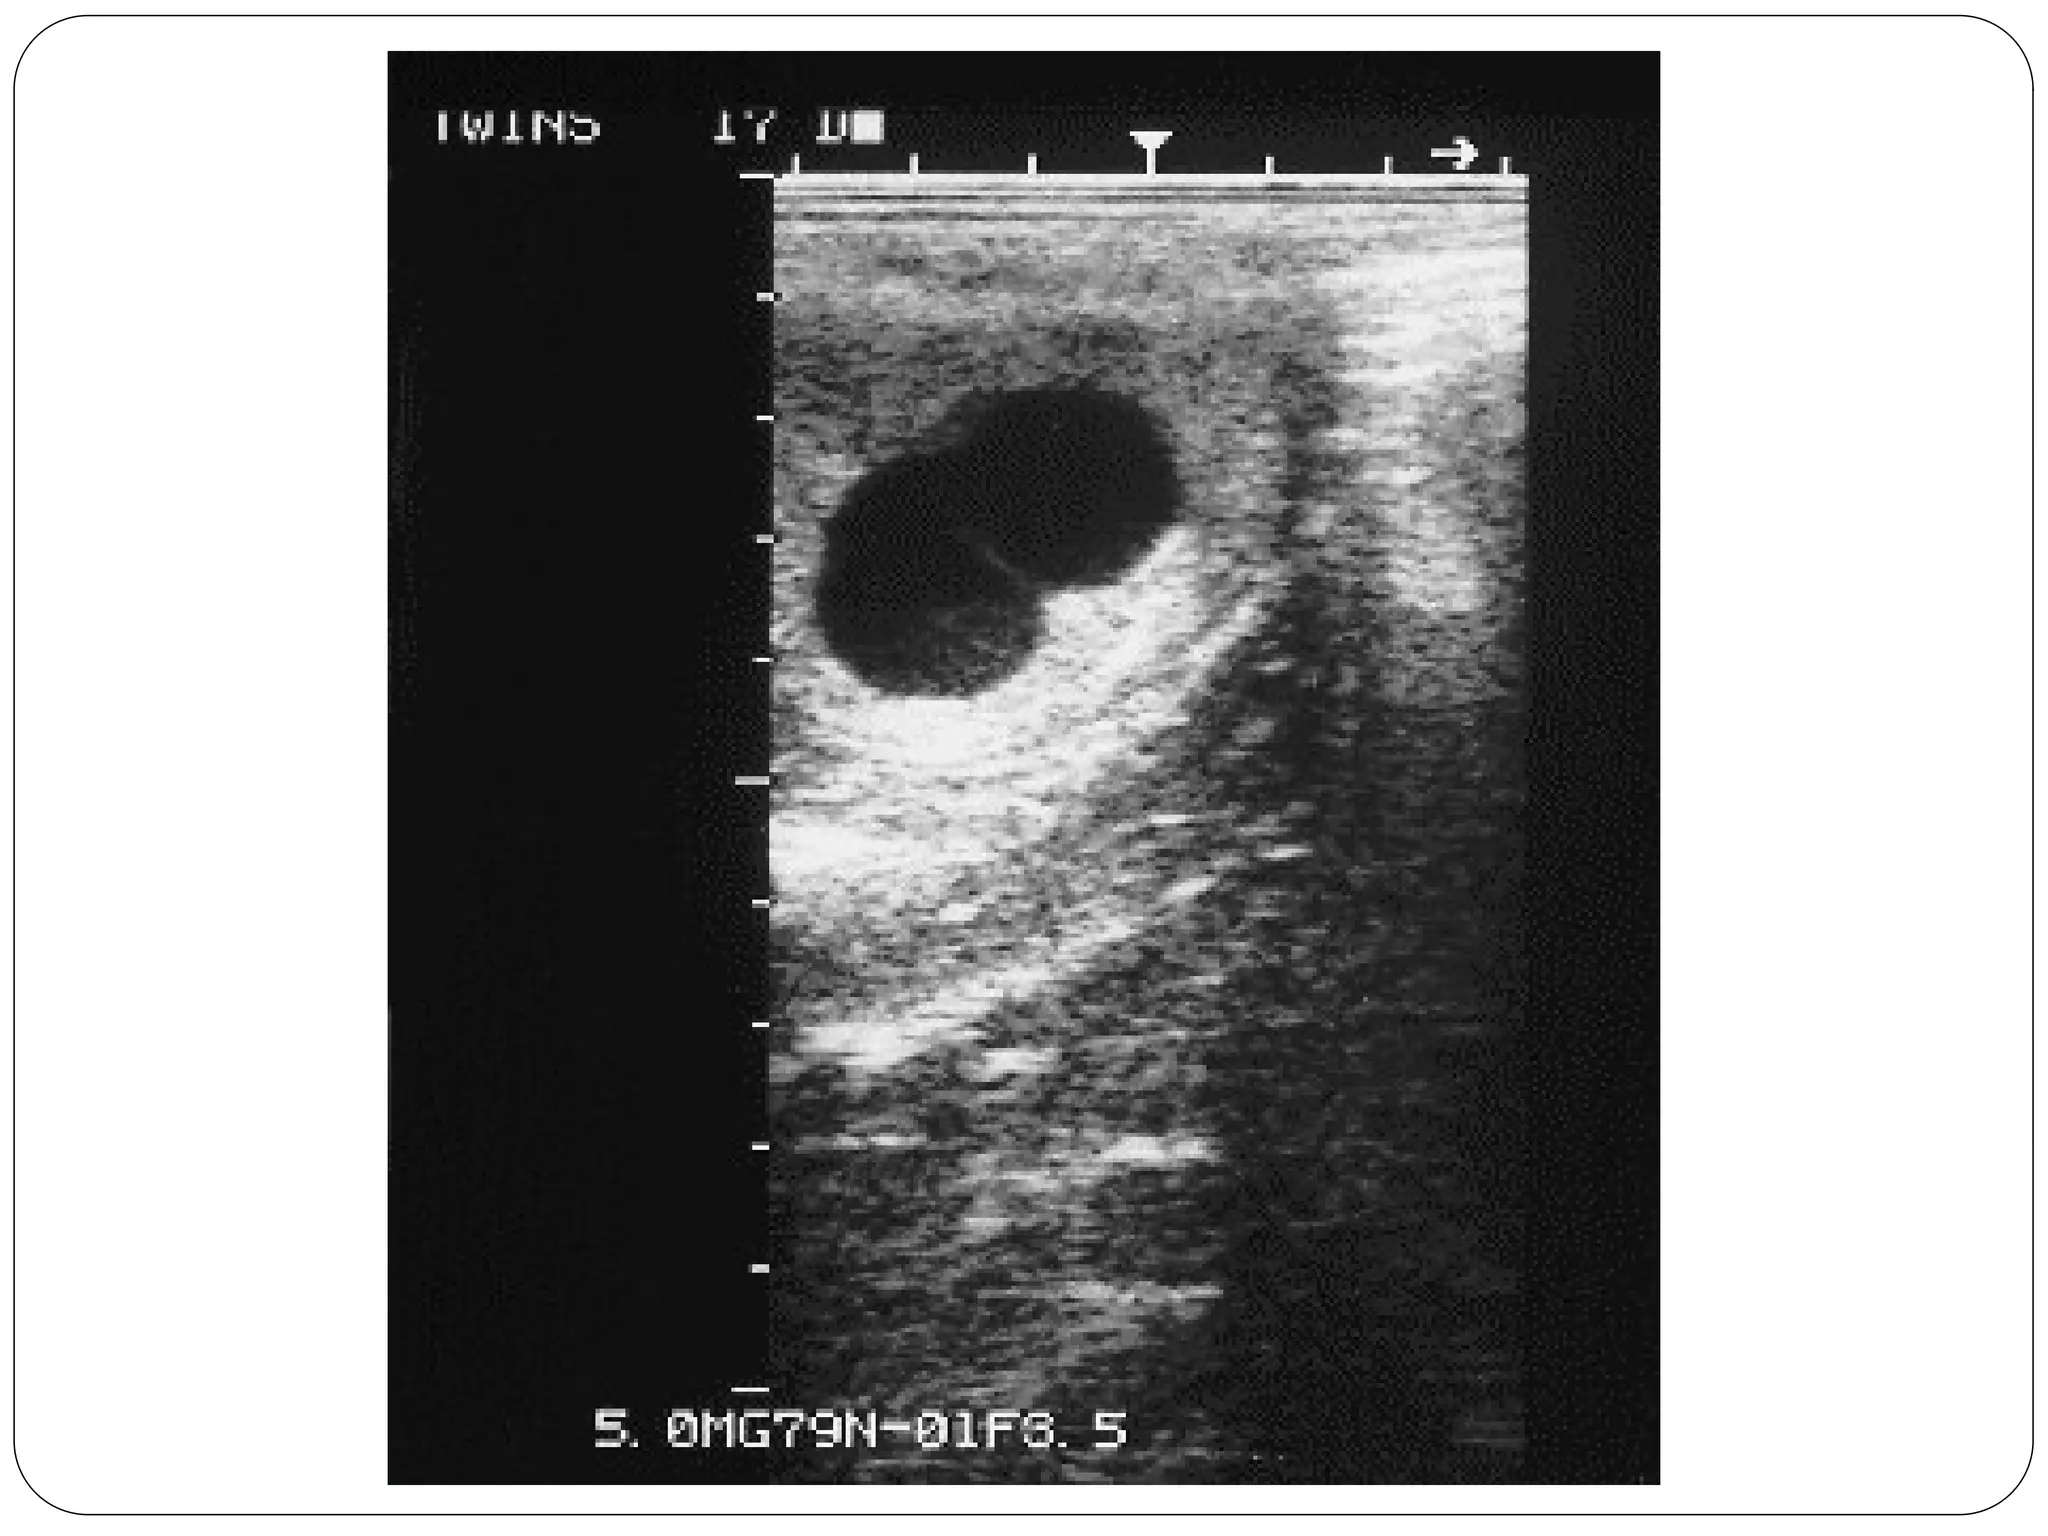

Twins (most common)

Monozygotic Twins…

Dizygotic twin pregnancy

Di-chorial and Di-amniotic.

Dyzygotic twins, are descended from a double ovulation and a double fertilization.

The 2 eggs are completely independent.

This configuration represents two thirds of all twin pregnancies.